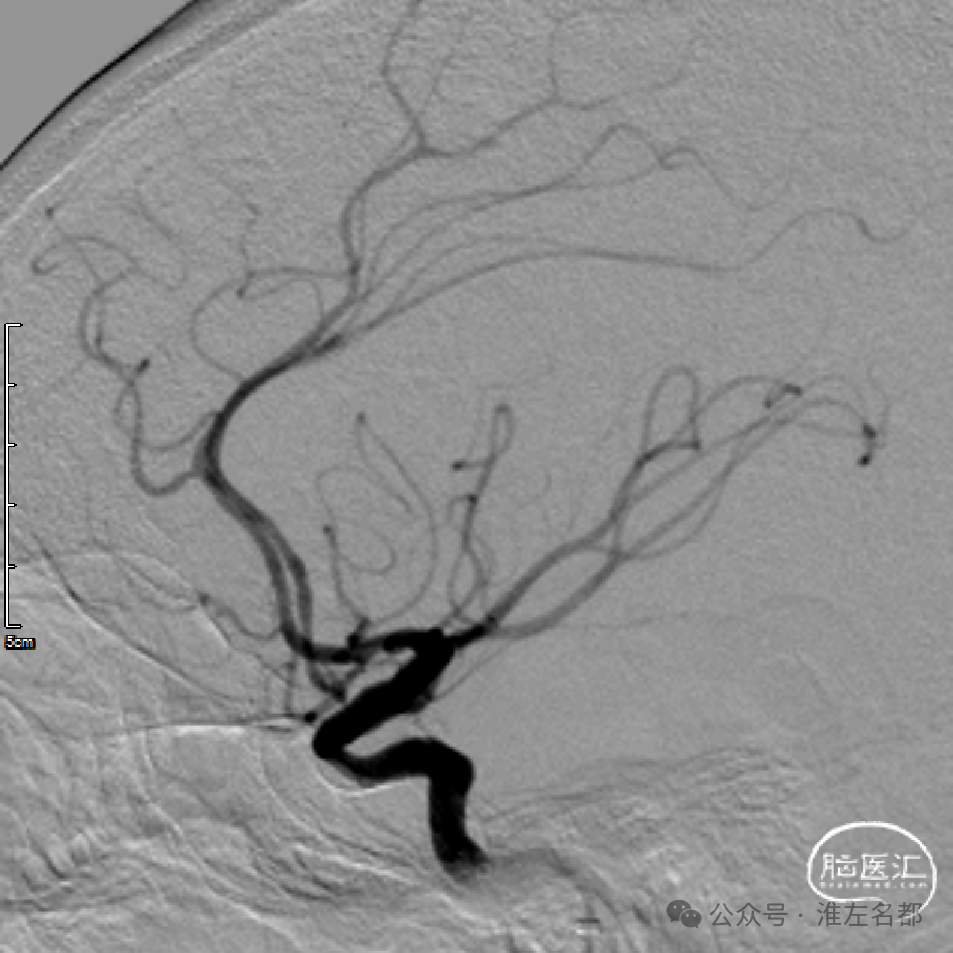

微导管通过闭塞位置,造影证实位于真腔。

经微导管释放取栓支架(S AB 4*20mm)后造影,前向血流恢复,局部狭窄(红箭)。